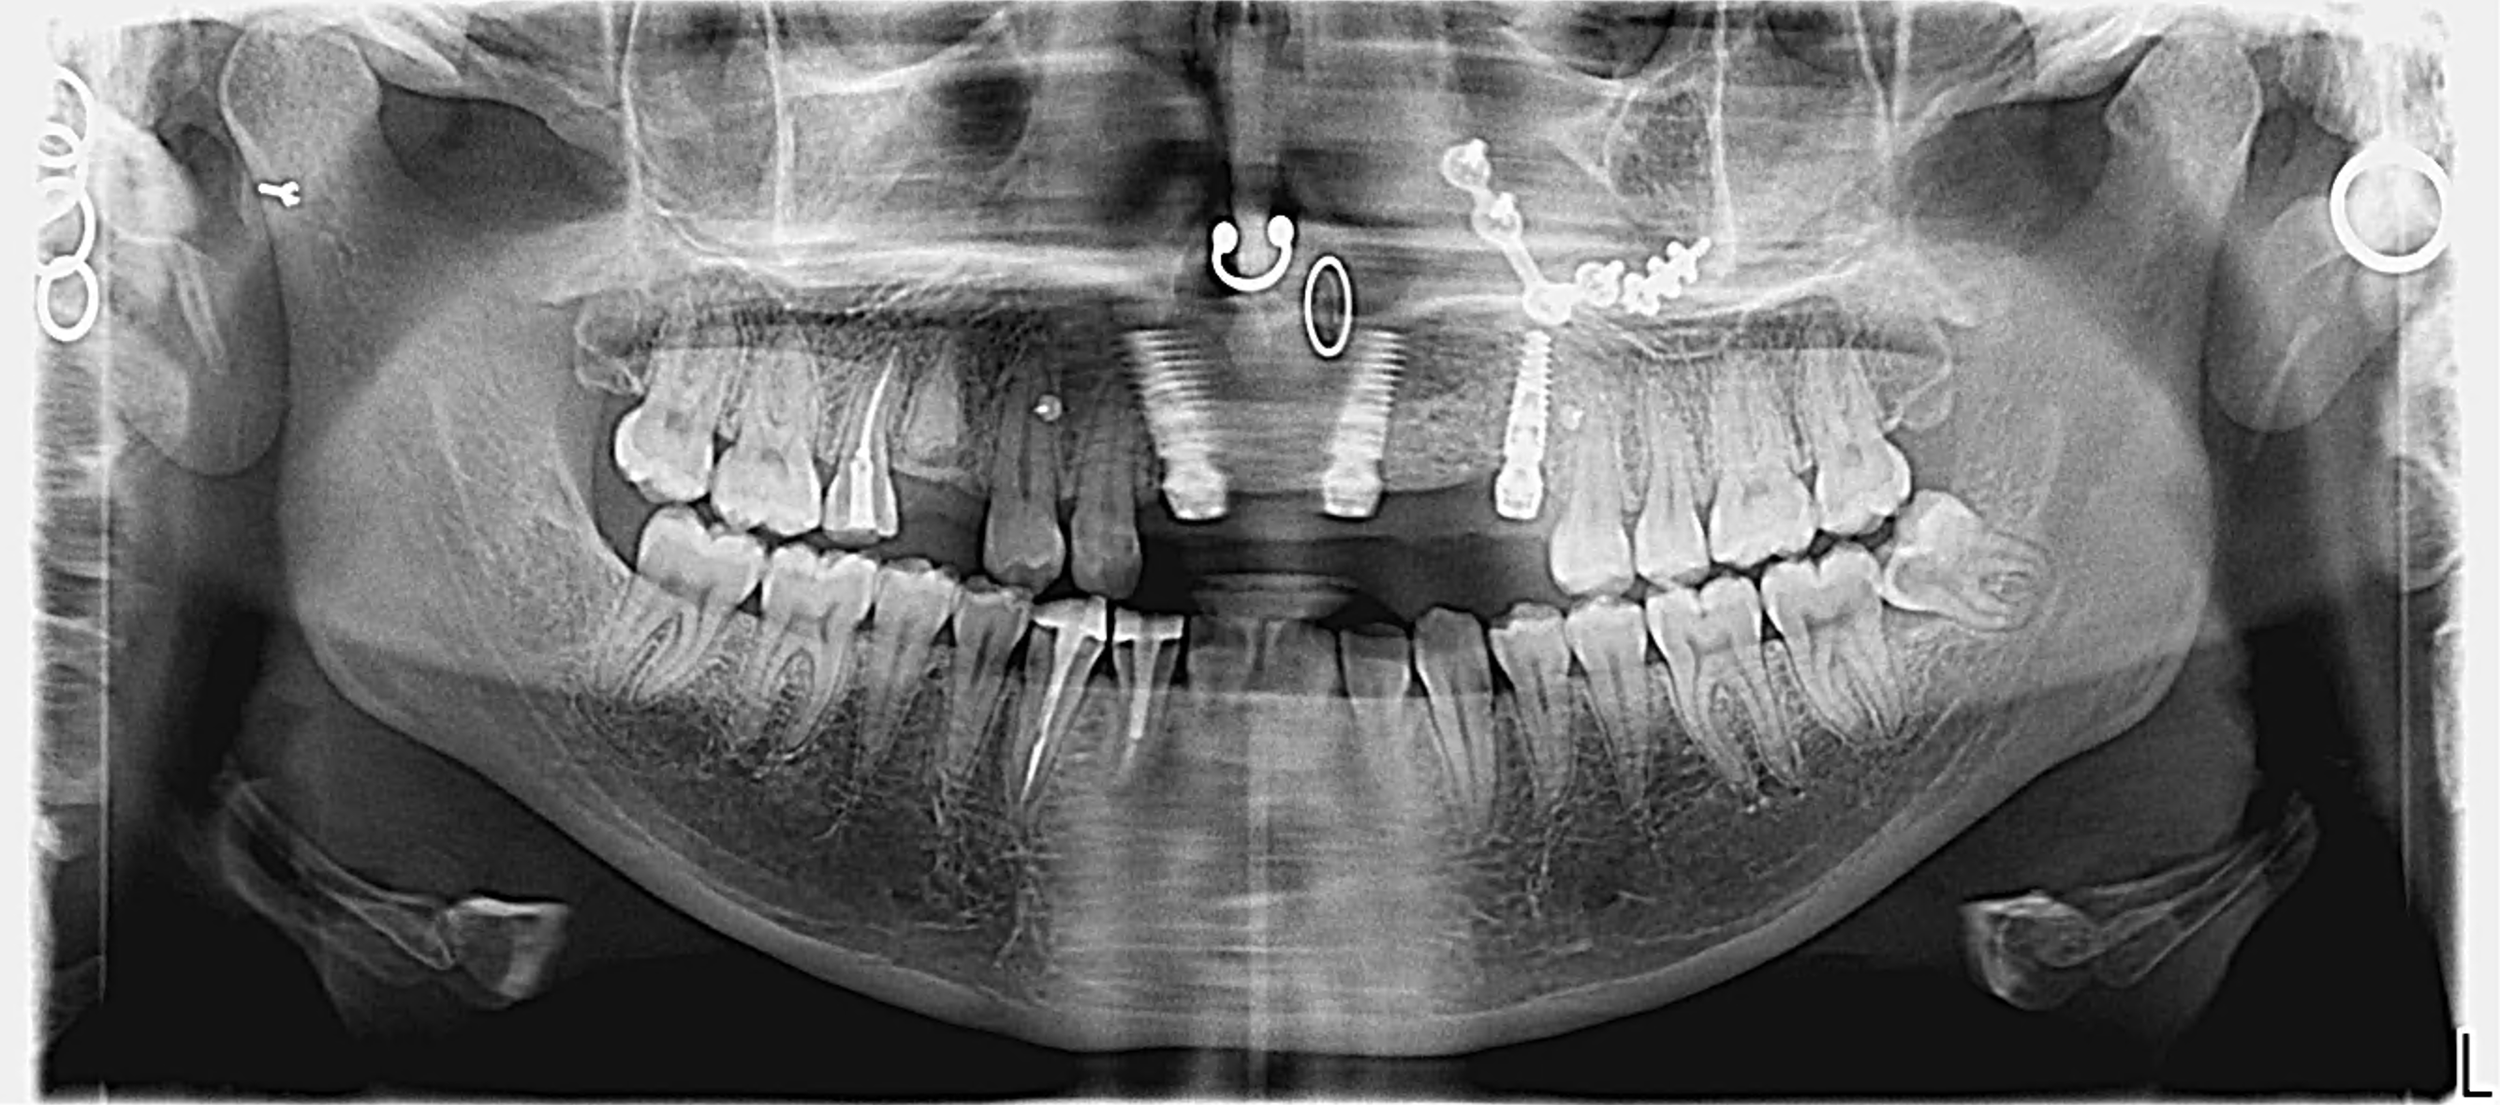

Eva a subit un accident grave de la route qui a conduit à la perte de ses dents ainsi que d’une perte d’os conséquente. Elle porte, à 20 ans, un dentier qui la complexe énormément et souhaite retrouver son sourire.

Après analyse de sa situation, nous avons opté pour un traitement mêlant greffe osseuse, implants dentaires et couronnes et restaurations céramiques.

Pour rétablir son sourire, nous avons réalisé une reconstruction d’os et de gencive sans prélèvement osseux à l’aide d’une technique de régénération osseuse guidée.

Après 6 mois de cicatrisation, le greffe est contrôlée et la mise en place des implants est planifiée par chirurgie guidée.

Seulement trois implants seront positionnés pour rétablir son sourire.